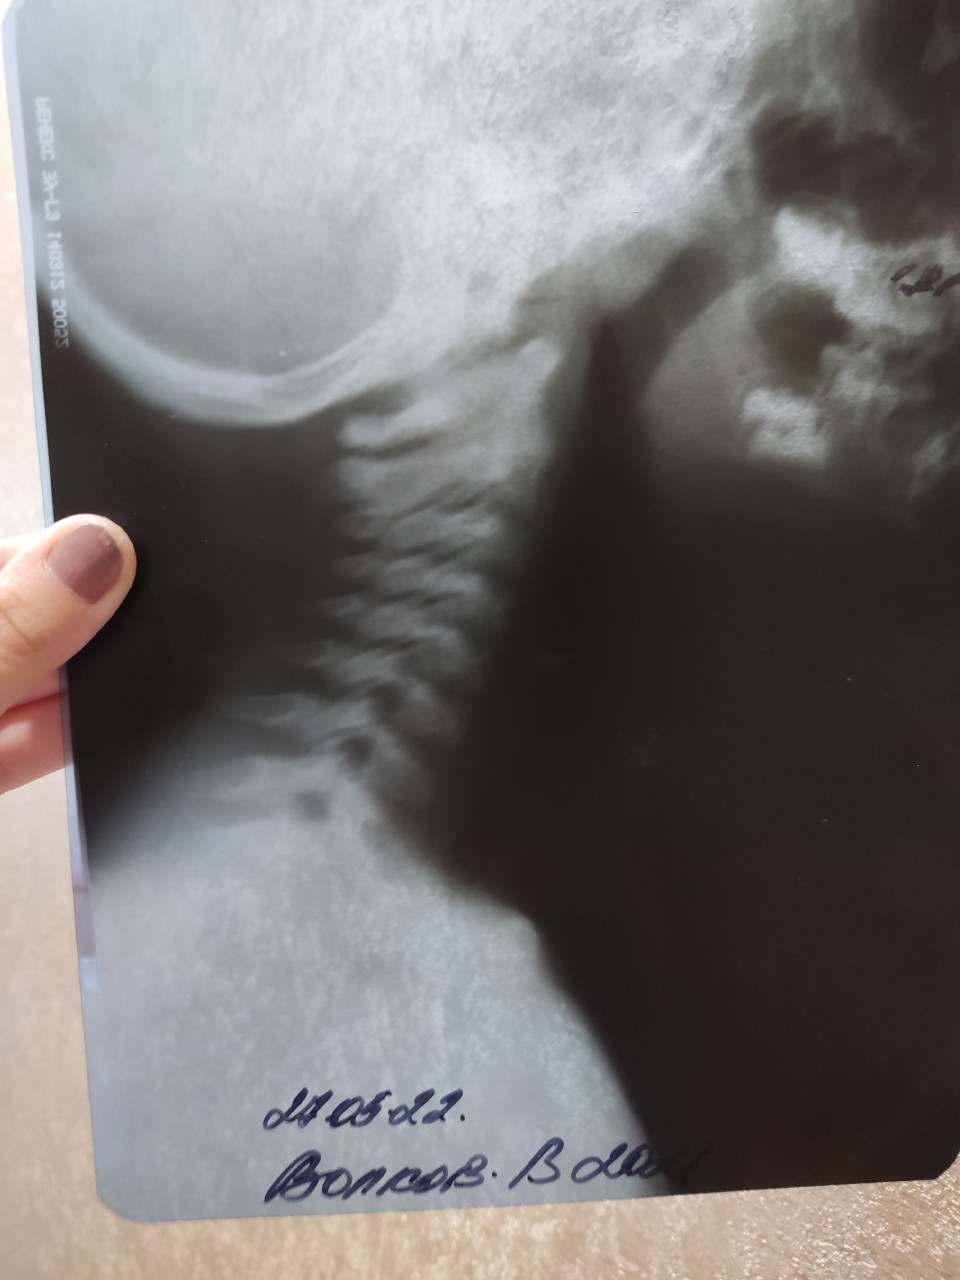

Рентгеновские технологии: усиленные экраны 35x35